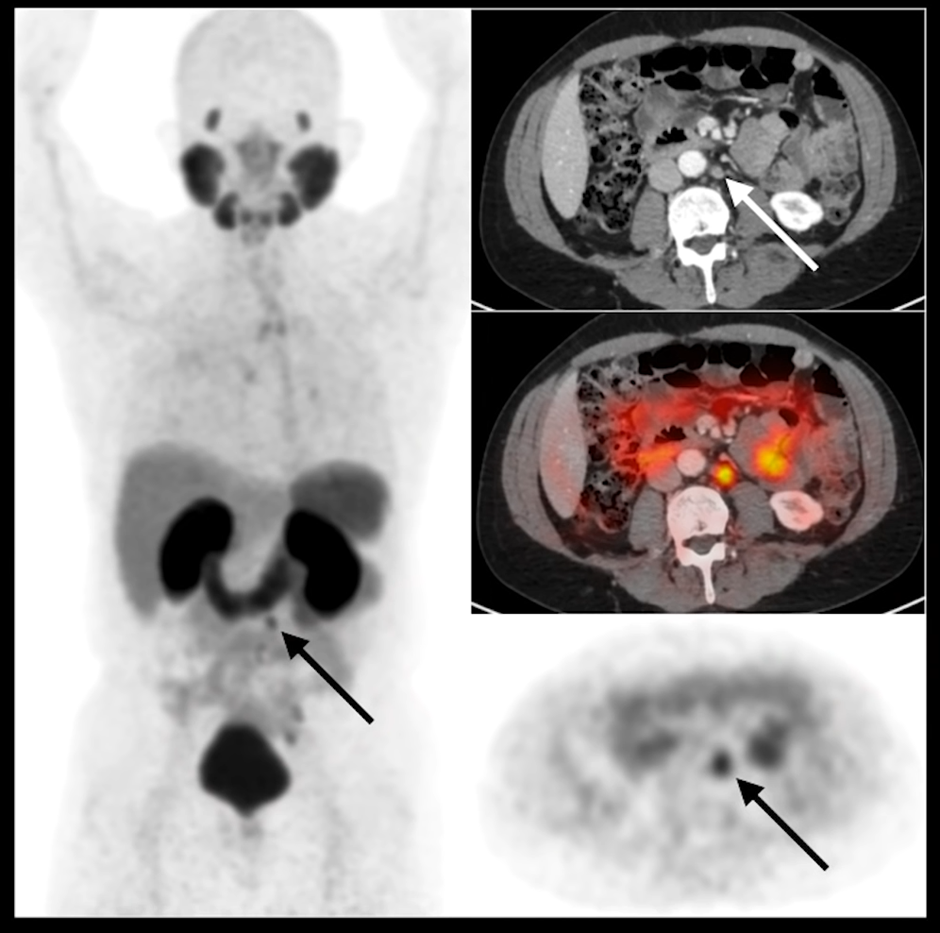

PSMA PET Scan Results

Scan results are interpreted by nuclear medicine physicians and radiologists.

Reports Typically Include:

- Location of lesions

- Number of suspicious areas

- SUV values indicating tracer uptake intensity

- Evidence of metastasis or recurrence

Understanding SUVmax

SUVmax refers to standardized uptake value maximum.

Higher SUV values may indicate:

- Increased tracer uptake

- Greater PSMA expression

- Higher suspicion for active disease

However, SUV interpretation must always be correlated with clinical context.